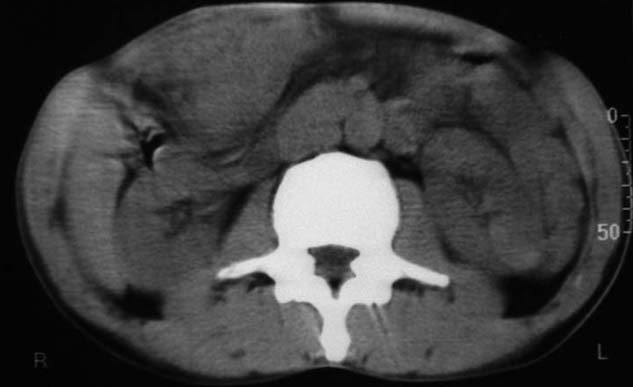

男,50y,右上腹包块痛10天,查:右上腹饱满,右肋下触及6*6cm大小包块,质硬,压痛。患者诉:10天前感冒胸闷,痛,后痛及右上腹部,既往有肝炎病史。

考虑:肝左内叶巨块型癌,主动脉旁淋巴结转移.(有一层面似见胆囊受压.)

我跟认为胆囊病变的可能性大,肠道准备不好,带来相关解剖结构的部位清晰。